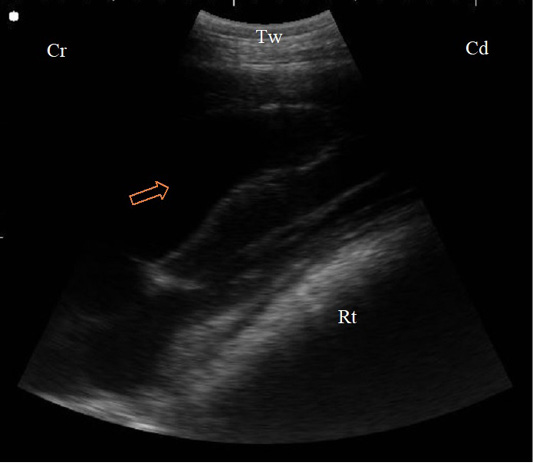

B. Mode sonogram in a case with localized traumatic reticulo-peritonitis. Thickened reticular wall (Rt) separated from the diaphragm (D) with an echogenic fibrinous mass and anechoic exudate (arrow) as imaged from the left 6th ICS, Aw: Abdominal wall, Cr: Cranial, Cd: Caudal.